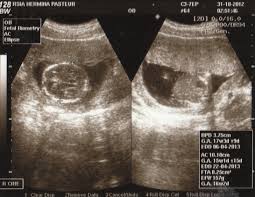

EDD dalam USG: 5 Poin Penting yang Perlu Ibu Hamil Tahu

Selamat datang, calon ibu! Saat Anda menjalani kehamilan, salah satu momen yang paling mendebarkan adalah menantikan hari kelahiran sang buah hati. Seringkali, saat Anda melakukan USG, dokter akan menyebutkan istilah EDD. Tapi, apa sebenarnya EDD dalam USG itu? Dan mengapa ini begitu penting untuk diketahui? Baca : USG: 5 Fakta Mengejutkan yang Wajib Ibu Hamil Tahu … Read more